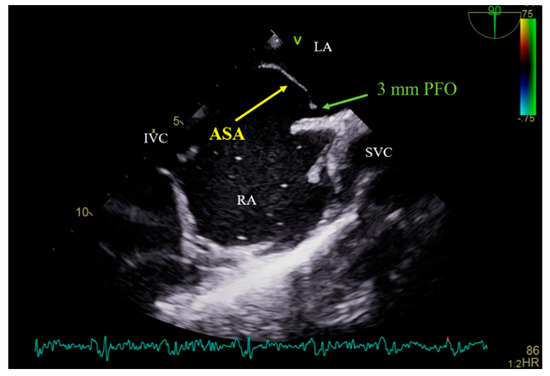

A 54-year-old female patient who suffered an ischemic stroke with transient right-hand paresis and motor dysphasia was admitted for a scheduled percutaneous transcatheter closure of the patent foramen ovale (PFO). Prior investigations, including the magnetic resonance imaging of the head and neck, 24 h Holter monitoring for arrhythmia, and blood testing for a hypercoagulable state, were performed and yielded unremarkable results. Subsequent diagnostic tests, including a transcranial Doppler (TCD) bubble test and saline contrast transthoracic echocardiography (TTE), revealed a right-to-left shunt at the level of the interatrial septum (IAS). This was confirmed by transesophageal echocardiography (TEE), which identified the presence of the PFO with an atrial septal aneurysm (ASA) and an abnormal septal excursion (Figure 1). Based on a thorough investigation, all the other potential causes of a cryptogenic stroke, such as major vessel atherosclerosis, small vessel disease, atrial fibrillation with cardioembolism, artery dissection, a hypercoagulable state, uncontrolled hypertension or diabetes mellitus, and autoimmune disease, were excluded. The diagnosis of a PFO-related stroke was established. Therefore, the percutaneous endovascular closure of the PFO was the management strategy of choice.

Figure 1.

Bicaval view TEE showing PFO with an atrial septal aneurysm. TEE—transesophageal echocardiography; PFO—patent foramen ovale; ASA—atrial septal aneurysm; LA—left atrium; RA—right atrium; IVC—inferior vena cava; SVC—superior vena cava.